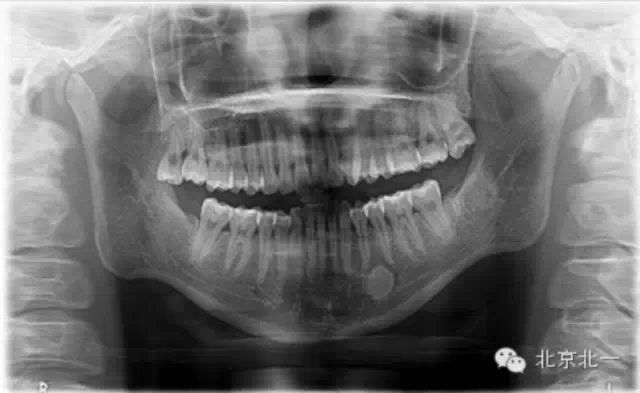

【口腔種植】致密性骨炎/牙骨質(zhì)增生/骨島如何鑒別?

頜骨三種高密度影像的鑒別

1)致密性骨炎

概述:

是指根尖周組織受到輕微緩慢持續(xù)性的低毒性因素刺激,而表現(xiàn)出以骨質(zhì)增生為主的防御性反應(yīng)。一般無自覺癥狀,多見于青年人,下頜第一磨牙多見,常有較大齲壞。

2)牙骨質(zhì)增生:

是由于齲壞、牙周炎、頜創(chuàng)傷等某些局部因素或全身疾患的影響,牙骨質(zhì)形成的異常增加。牙骨質(zhì)增生可發(fā)生于一個或者多個牙,多無臨床癥狀。

3)骨島:

主要和根尖型骨島鑒別,主要集中位于根尖區(qū)的骨島,